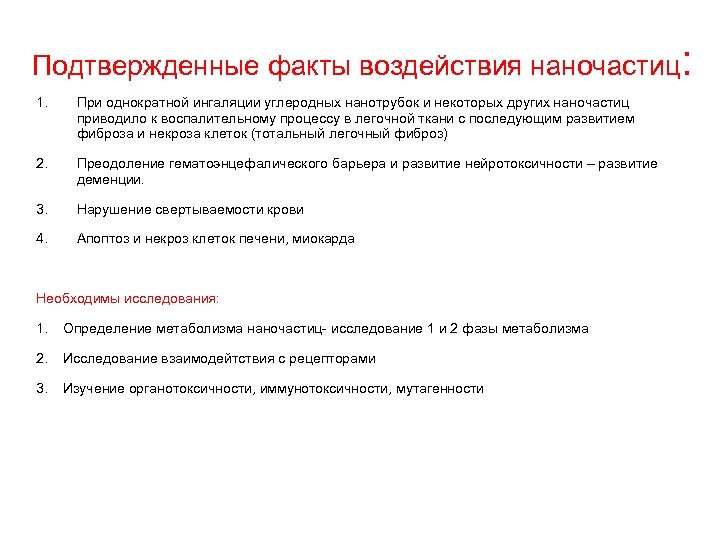

Особенности профессиональной патологии на современном этапе: 1. Ликвидация многих предприятий. 2. Развитие новых отраслей, технологий, использование новых химических соединений, влияние на организм которых не изучено, широкое воздействие электромагнитных волн. 3. Развитие частного производства: 81% частная собственность 12% государственная собственность. 7% другие виды собственности 3. Отсутствие тяжелых форм профессиональной патологии в связи с уровнем концентраций вредных веществ и вредных факторов на уровне ПДК или ПДУ. Изменение течение профзаболеваний. Возможно многие заболевания имеют профессиональную этиологию. 4. Наличие общей патологии, которая может быть обусловлена производственными вредностями. 5. В настоящее время стирается грань между производством и окружающей средой: бытовая химия шум магнитные поля видеодисплейные терминалы (компьютеры) нанотехнологии

Особенности профессиональной патологии на современном этапе: 1. Ликвидация многих предприятий. 2. Развитие новых отраслей, технологий, использование новых химических соединений, влияние на организм которых не изучено, широкое воздействие электромагнитных волн. 3. Развитие частного производства: 81% частная собственность 12% государственная собственность. 7% другие виды собственности 3. Отсутствие тяжелых форм профессиональной патологии в связи с уровнем концентраций вредных веществ и вредных факторов на уровне ПДК или ПДУ. Изменение течение профзаболеваний. Возможно многие заболевания имеют профессиональную этиологию. 4. Наличие общей патологии, которая может быть обусловлена производственными вредностями. 5. В настоящее время стирается грань между производством и окружающей средой: бытовая химия шум магнитные поля видеодисплейные терминалы (компьютеры) нанотехнологии